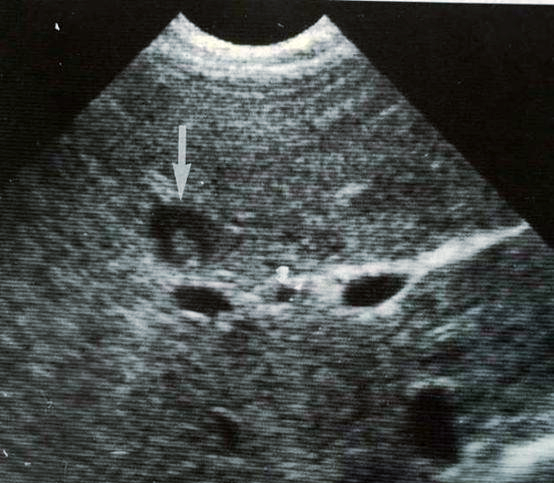

消化系统肿瘤肝脏转移,肾转移,典型牛眼征

结肠癌牛眼肝转移的超声图像照片摄影图片